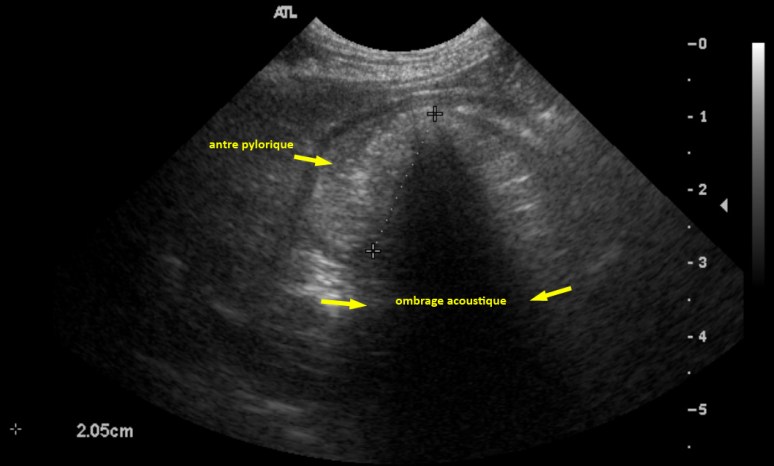

L’échographie a d’abord révélé un estomac rempli de liquide et de matériel hyperéchogène en région déclive (Image écho 1), puis une structure hyperatténuante provoquant un ombrage acoustique presque complet dans le corps et l’antre de l’estomac (Images écho 2 et 3). Comme la nourriture normale ne devrait pas engendrer d’ombrage complet (à ne pas confondre avec un ombrage trouble souvent associé à la présence de nourriture et d’air), ce signe a été interprété comme signe convaincant de corps étranger ! Comme ce corps étranger était mobile, il a bougé entre les radios et l’échographie.